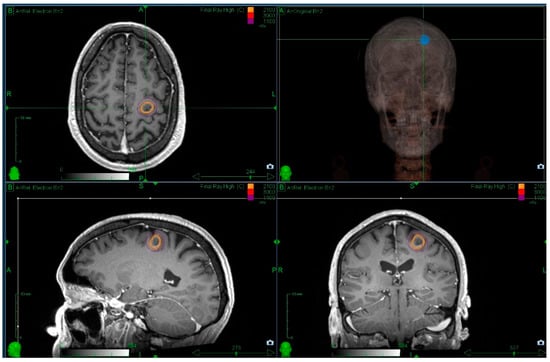

3.2. Radiosurgery Following Surgical Resection